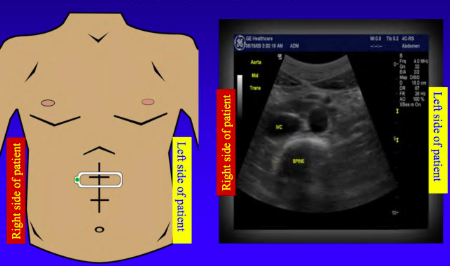

What is the transducer display in this image?

linear (rectangle)